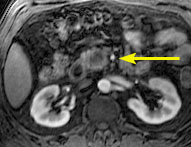

In this sub-second coronal MR cholangio-pancreatography image, the the mass is shown to obstruct the pancreatic duct (arrow).